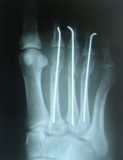

1. Ηallux valgus of the right foot in a 28-year-old female.

Treatment: Scarf osteotomy of the first metatarsal

I. Anteroposterior x-ray foot during procedure shows the scarf osteotomy with two screws II. This image shows the foot in a standing position one year down the line from the procedure. The young lady is very happy.